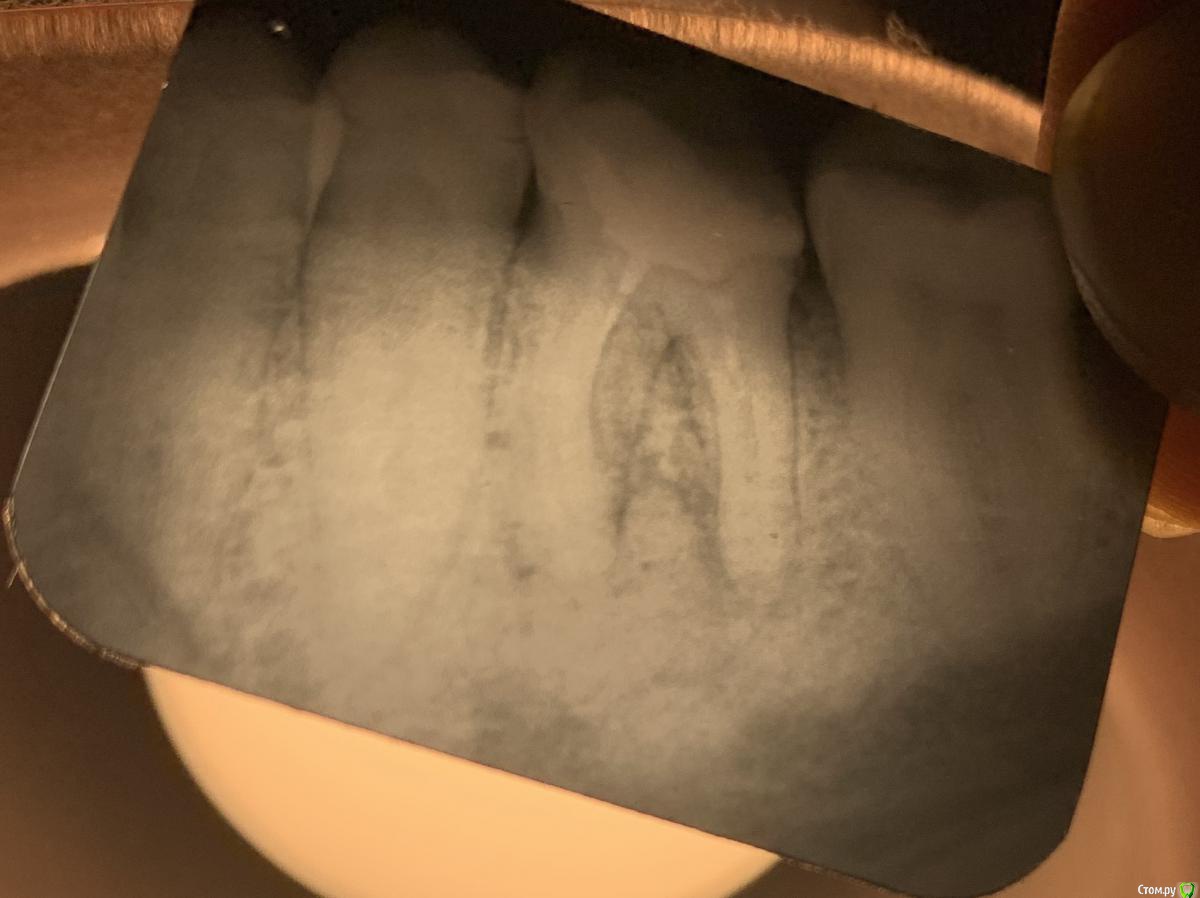

lodo4nik Опубликовано 22 апреля, 2021 Автор Поделиться Опубликовано 22 апреля, 2021 (изменено) 11.08.2020 в 07:43, red_butler сказал: тему можно закрывать, или поделитесь результатом лечения и протезирования? Пожалуй можно и поделиться ? Зуб пролечен и сохранен. Лечение происходило в три посещения. 1. Прошли каналы, заложили временную пломбу на 6 месяцев. Все это время не жевал на эту сторону. Один раз приходил обновить пломбу-стиралась. 2. Пришел к врачу на 1.5 месяца позже установленного (7.5 мес). Что то сделала, поменяла временную пломбу и отправила еще на 1 месяц. Объяснила чем то рыхлым-то ли тканями, то ли каналами. 3. Окончательная пломбировка и восстановление жевательной поверхности. Контрольный рентген через год и через два. Спасибо большое red_butler, за то, что придали уверенности в нужный момент. Изменено 22 апреля, 2021 пользователем lodo4nik 1 Ссылка на комментарий

red_butler Опубликовано 22 апреля, 2021 Поделиться Опубликовано 22 апреля, 2021 47 минут назад, lodo4nik сказал: Спасибо большое red_butler, за то, что придали уверенности в нужный момент. пожалуйста, только обязательно восстановите зуб коронкой, иначе всё напрасно Ссылка на комментарий